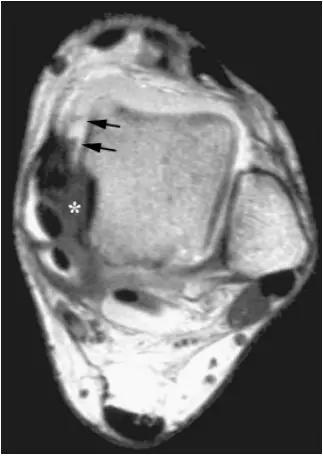

影像学表现为距骨胫骨间肌腱及趾长屈肌腱水肿、增厚,内踝及距骨后内侧骨赘形成。

轴位示意图示后内侧撞击综合征:M:内踝;L:外踝;TP:胫后肌腱;FDL:趾长屈肌腱;Talus:距骨。短箭:距骨胫骨间肌腱深层纤维;箭头:距骨胫骨间肌腱后部纤维。

X线平片示胫骨后部骨赘形成,MR质子像黑箭示胫骨内后侧骨赘形成,白箭示内后侧软组织增厚, 白箭头:胫后肌腱;黑箭头:趾长屈肌腱